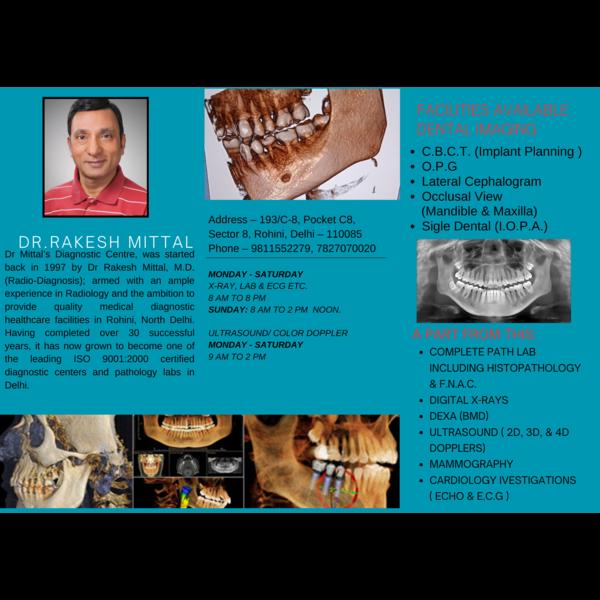

Cbct in delhi ncr, new delhi Cone Beam Computed To...

Dental scan near me c-8/193 sector 8 rohini delhi...

View DetailsCBCT IN DELHI C-8/193 SECTOR 8 ROHINI DELHI-110085...

CBCT test in rohini#delhi NCR CBCT stands for con...

CBCT IN DELHI C-8/193 SECTOR 8 ROHINI DELHI-110085...

Cbct scan near me Dr. Mittal's Diagnostic centre s...

CBCT in delhi CBCT in rohini CBCT stands for cone...